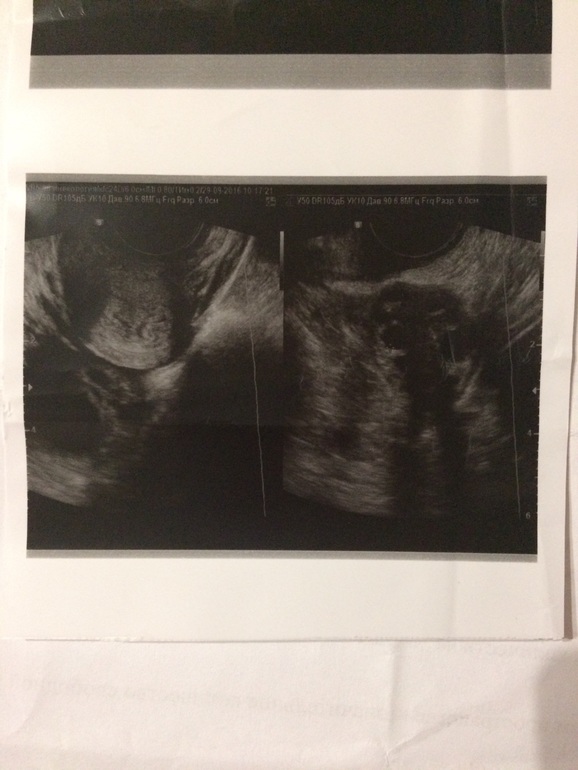

14 дц, ДФ в правом яичнике 21мм 16 дц, ЖТ 17 мм

Когда я задала вопрос такой же своему гинекологу, как отличить ЖТ от ДФ, она говорит это сразу видно, также у ЖТ есть признак, это кровоток вокруг (если правильно назвала), типа как на фото

14 дц, ДФ в правом яичнике 24*19 мм 15 дц, ЖТ 14*10мм

13 дц, проовулировавший фолликул 11мм